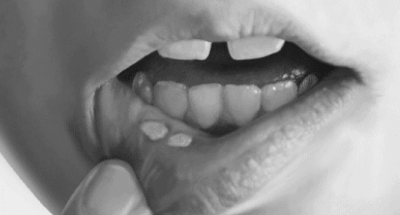

- Травматичний стоматит розвивається у дітей трьох років в результаті пошкодження слизової оболонки ротової порожнини. Переноситься такий стоматит досить легко, при цьому відсутнє підвищення температури тіла і ослаблення організму дитини.

- Афтознийстоматит є одним із складних і серйозних захворювань, хоча причини його виникнення у дітей до цих пір не встановлені. Найчастіше ця патологія діагностується у дітей до року і старше, які страждають такими захворюваннями, як:

Утворилися на слизовій оболонці виразки можуть доставляти малюкові больові відчуття, тому рекомендується використовувати знеболюючі препарати перед сном або прийомом їжі. Для цих цілей дитині можна застосовувати спеціальні гелі, основним складовим речовиною в яких є Лідокаїн. Ці препарати не тільки надають охолоджуючий ефект на уражену поверхню слизової, а й миттєво знімають больові відчуття.